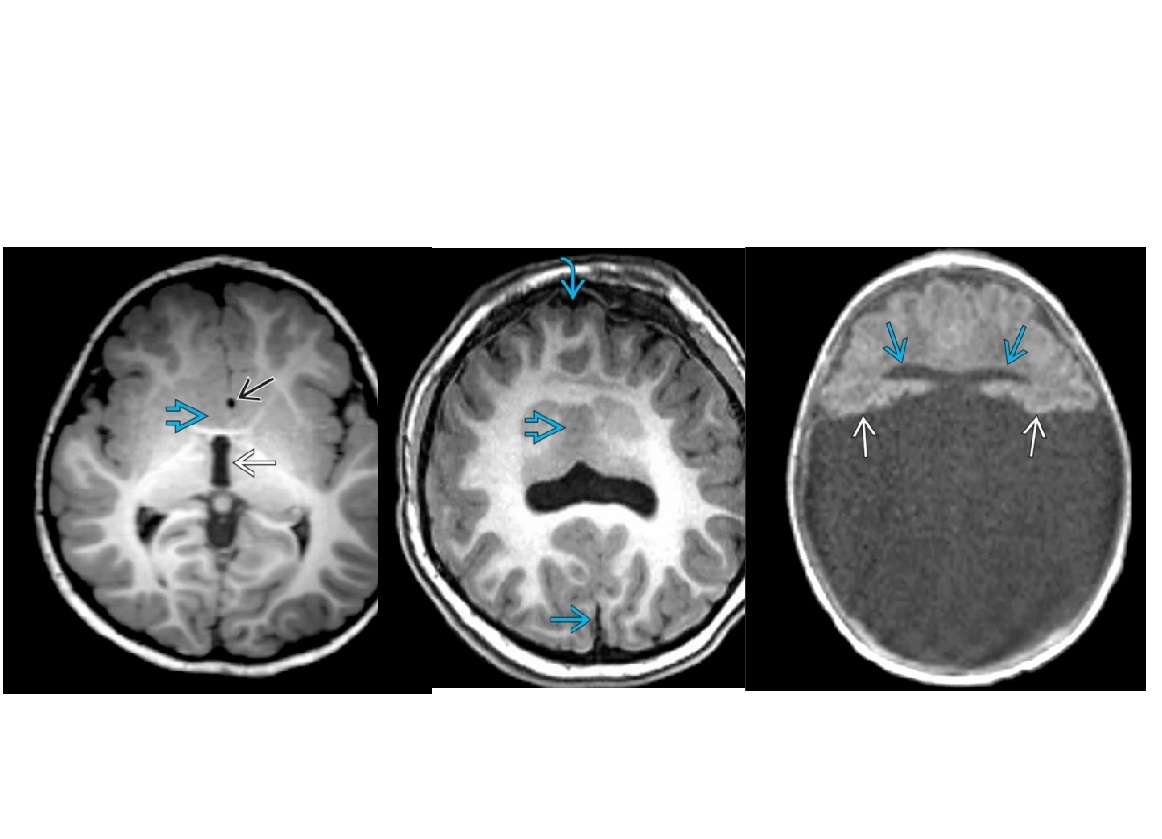

What brain tumour is found in Tuberous Sclerosis?

A

Subependymal giant cell astrocytoma (SEGA)

aka Intraventricular astrocytoma of tuberous sclerosis complex (TSC

Enlarging, enhancing foramen of Monro mass in patient with TSC

Tuberous sclerosis is triad of

-facial angiofibromas

-seizures

-mental retardation

Cortical/subcortical TUBERS

- expand overlying gyri, low on CT,

- can have cystic and Ca2+ transformation.

DDX - TORCH namely toxo and CMV can cause periventricular Ca2+